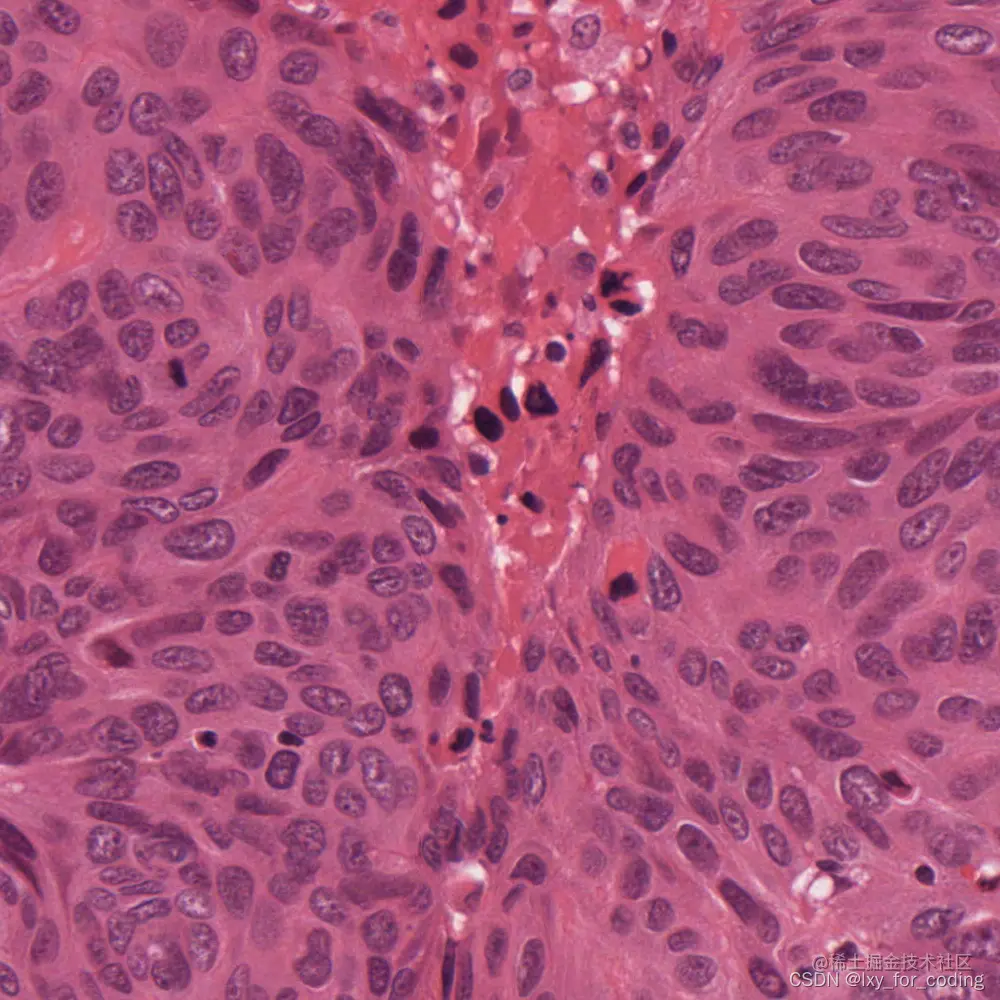

实验数据集示例:

在这里插入图片描述(标注)

在这里插入图片描述